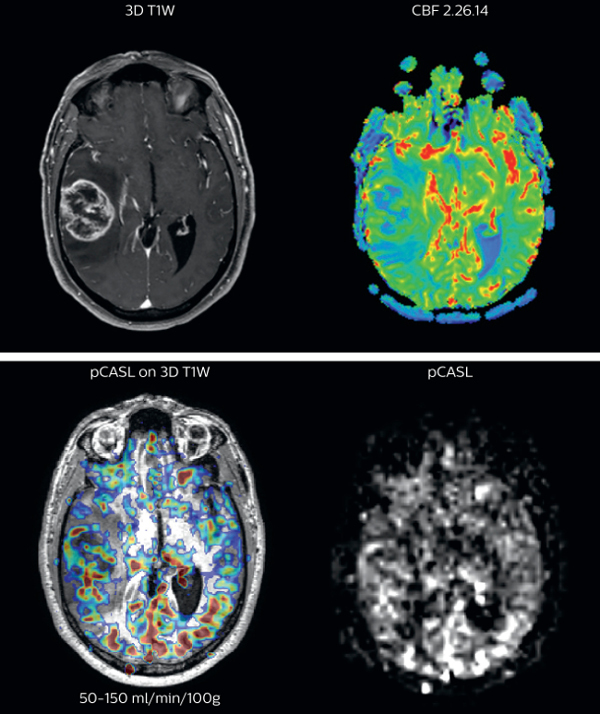

Cerebral blood flow in glioblastoma

The pCASL perfusion map overlaid on the 3D T1 image demonstrates a peripheral rim of elevated cerebral blood flow corresponding to the centrally necrotic glioblastoma.

The pCASL-generated CBF closely approximates the rim of elevated rCBV obtained with DSC contrast-enhanced perfusion imaging.

Scanned on Achieva 3.0T dStream